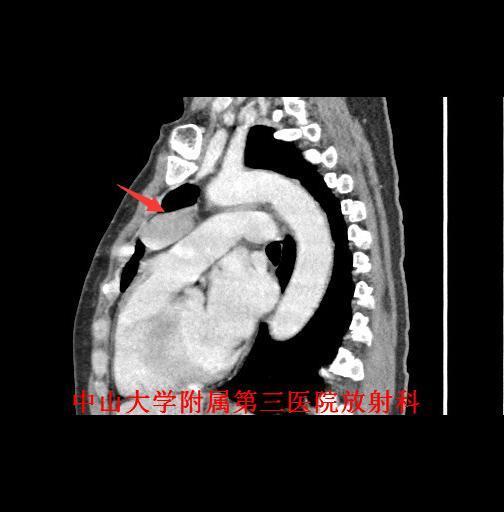

主诉:咳嗽咳痰1月余,发现前纵隔肿物4天。 病史:老年女性,慢性病程。患者于1月余前出现反复咳嗽,咳痰,无痰中带血及咯血,遂至我院门诊就诊,行胸片及胸部CT检查提示“前纵隔肿物,胸腺瘤?”。

查体:胸廓对称无畸形,无挤压痛,呼吸运动度及语颤对称,双肺叩诊清音,呼吸音清晰。 辅查:胸部CT示:前纵隔肿物,胸腺瘤?

诊断:胸腺瘤。 治疗:排除手术禁忌症,于全麻下行“正中开胸胸腺扩大切除术”,病理提示:(胸腺肿物)符合胸腺瘤(AB型);免疫组化结果(②):CK(+),Vim(部分+),EMA(-),CK7(+),CK19(+),CK20(-),TdT(-),CD5(淋巴细胞+),CD1α(淋巴细胞+),Ki-67(淋巴细胞约60%+)。

讨论:胸腺瘤是前纵隔最常见的肿瘤,约占成人前纵隔肿瘤的50%。目前,CT是公认的早期检出及诊断胸腺瘤的最佳方法。CT一般表现为:圆形、卵圆形或分叶状肿块,边界清晰,多数密度均匀,可见钙化;大部分肿瘤生长不对称,居于前纵隔的一侧;直径<2cm的胸腺瘤可仅表现为正常胸腺边缘局部隆起;增强扫描仅有轻度强化。主要应与胸腺增生鉴别,后者胸腺体积弥漫性增大,以左右两叶增厚为主要特征,但仍保持正常形态,而胸腺瘤为局部结节。 参考文献:杨蕊梦,许乙凯,冯婕等.胸腺瘤的MSCT-病理-临床综合诊断[J].放射学实践,2007,22(7):711-713.